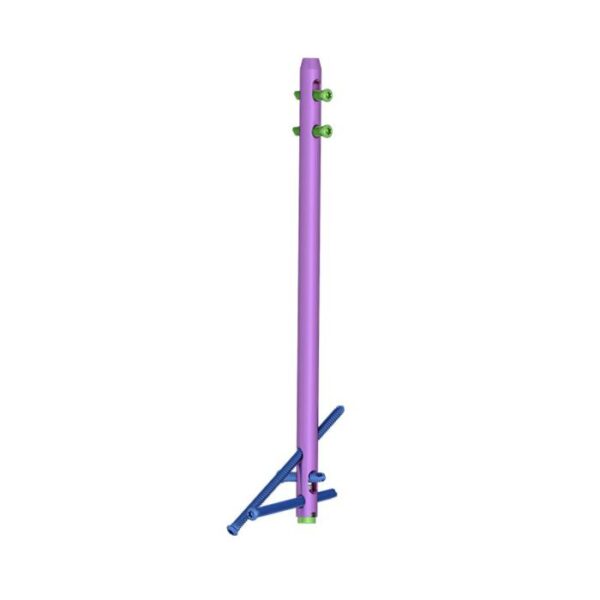

Clavo de artrodesis de tobillo:

- Proporcione diferentes diámetros y longitudes para más opciones clínicas.

- Los diferentes colores son fáciles de distinguir.

Tuerca de compresión en el orificio deslizante distal:

- El orificio deslizante distal permite una distancia máxima de compresión de 5 mm.

Orificios de bloqueo estáticos y dinámicos:

- Proporcione orificios de bloqueo estáticos y dinámicos en el proximal.

Tornillos distales para cepillado múltiple que cruzan los orificios de bloqueo:

- Fijación de articulaciones cruzadas para mejorar la estabilidad de la fusión.

- El tornillo se inserta oblicuamente en la apófisis anterior del calcáneo o en la articulación calcáneo-cuboidea para mejorar la fuerza y la estabilidad de extracción.

Eje direccional de carbono de cinco dedos:

- Una pieza de eje de puntería que está hecha de material de fibra de carbono garantiza la precisión de bloqueo.

- Simplifique el proceso de operación y acorte el tiempo de operación.